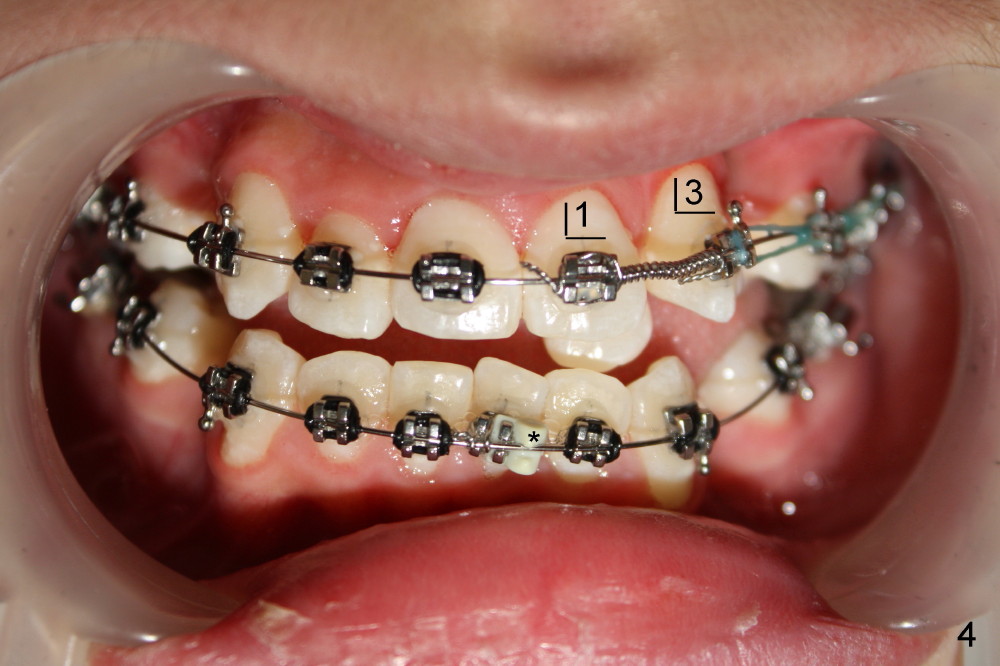

David, 16 years old, has severe crowding, midline deviation (Fig.1: dashed lines), and UL2 complete blockout (Fig.3: 2). Orthodontic treatment starts with extraction of four of the 1st bicuspids (Fig.2,3: .014 Niti).

Five weeks later, .018 ss wires are installed with open coil spring between UL 1 and 3 and power chain between UL 3 and 7 (Fig.4). Three months post-bracketing, space is being created for UL 2 (Fig.5). Four months post-bracketing, a lingual button is placed on UL2 with power chain x7 (Fig.6: sling shot); Pletcher's spring between UL 3 and 7 (^).

The alignment of UL2 improves one month of using .016x.022 ss wire with introduction of torque (total 14 months of treatment, Fig.17). The open bite (Fig.1-4, ignored), basically corrected nearly in the end of treatment (Fig.13-15), relapses < 2 years.